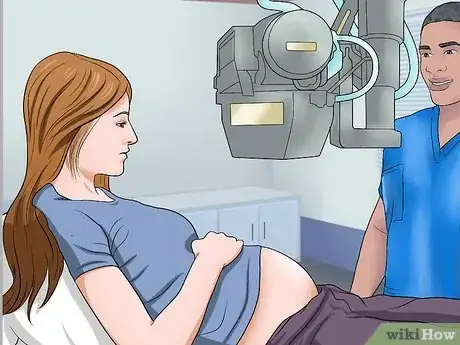

1Consult your doctor before the procedure. It is essential that you talk to your doctor before getting an X-ray, especially if you are breastfeeding or if you are or think you might be pregnant. You will be exposed to small amounts of radiation that can be dangerous for the developing fetus.[2]

- Depending on the circumstance, another imaging test might be used to avoid radiation.

- Warn your doctor or X-ray technician if you are or may be pregnant.⧼thumbs_response⧽